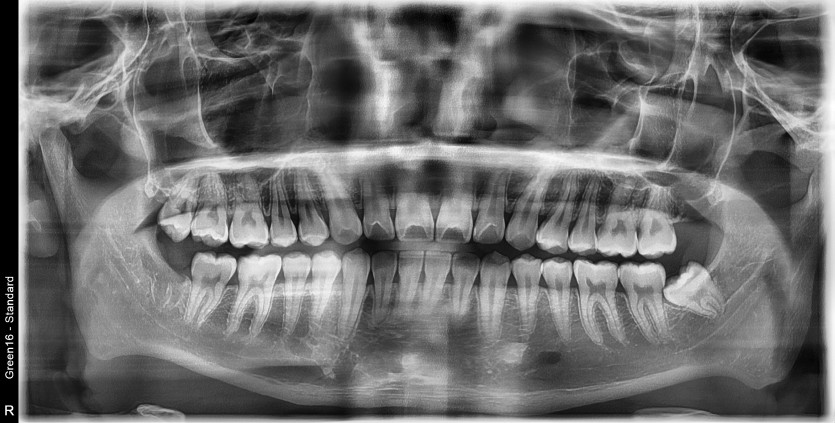

#48 사랑니 발치

구강 외과 전문의가 당일 발치했습니다.